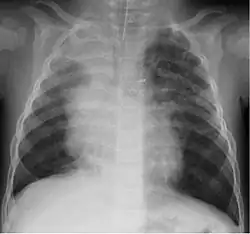

A study in Jordan found that 9% of 220 children hospitalized with lower respiratory tract infection were infected with bocavirus.[30] Of those infected the median age was 4 months. Coughing (100%), wheezing (82.7%) and fever (68.2%) were the most common clinical findings with bronchopneumonia (35%) and bronchiolitis (30%) being the most common ultimate diagnoses.

Although most cases are mild, severe respiratory disease has also been reported.[31]